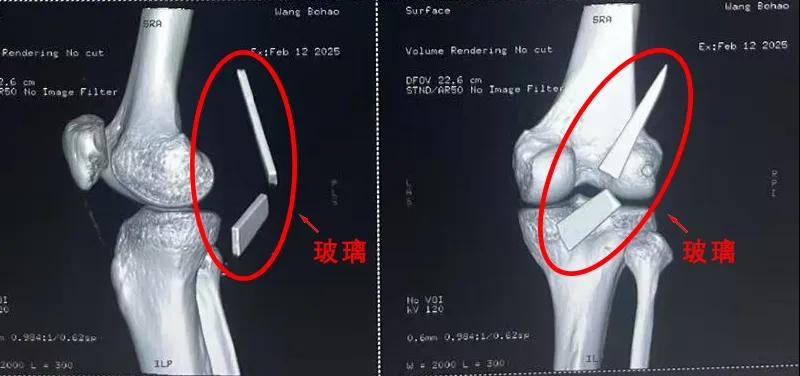

患者家屬這才開(kāi)始意識(shí)到問(wèn)題的嚴(yán)重性,便帶著孩子到鄉(xiāng)鎮(zhèn)衛(wèi)生院檢查——結(jié)果顯示右膝關(guān)節(jié)后方竟然殘留著兩塊兒鋒利的碎玻璃,測(cè)量后預(yù)估玻璃總長(zhǎng)將近13厘米!

由于玻璃位置毗鄰坐骨神經(jīng)和股動(dòng)脈,一旦刺破股動(dòng)脈,將嚴(yán)重威脅生命。家屬著急萬(wàn)分,想著能否盡快手術(shù)取出碎片,于是慕名來(lái)到漯河醫(yī)專(zhuān)二附院(漯河市骨科醫(yī)院、漯河市立醫(yī)院)手顯微外科(修復(fù)重建骨感染科)。

術(shù)中,馬廣輝醫(yī)生憑借扎實(shí)的理論知識(shí)和嫻熟的顯微外科技術(shù),順利找到深深刺進(jìn)肌肉的兩塊玻璃,肉眼可見(jiàn)玻璃尖端距股動(dòng)脈僅有不到半公分的距離!如果患者再耽誤半天或者再多活動(dòng)幾次膝關(guān)節(jié),小指粗的股動(dòng)脈很有可能被玻璃扎破,后果難以想象。

最終,馬廣輝醫(yī)生在血管、神經(jīng)表面順利取出兩塊玻璃碎片,拆除了埋在患者膝關(guān)節(jié)的“炸彈”。在告知患者家屬術(shù)中情況后,家屬懸著的心終于放了下來(lái)。